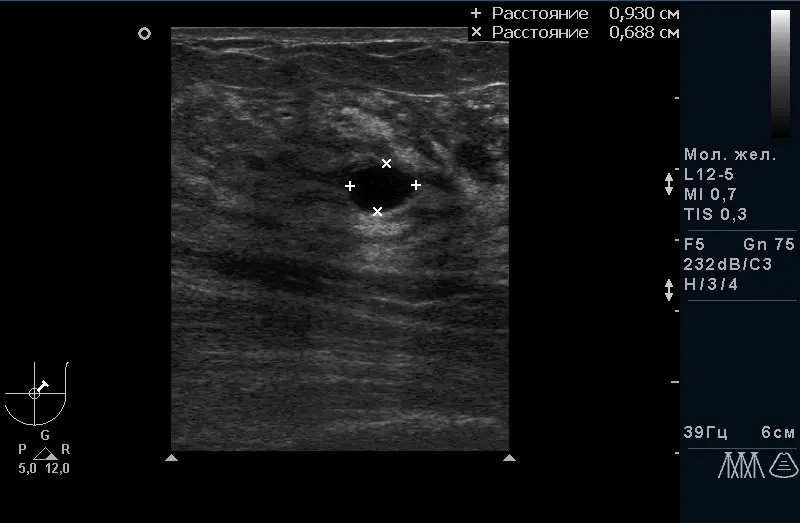

Рис.1. Фіброзно-кістозна мастопатія з кістозним компонентом. |